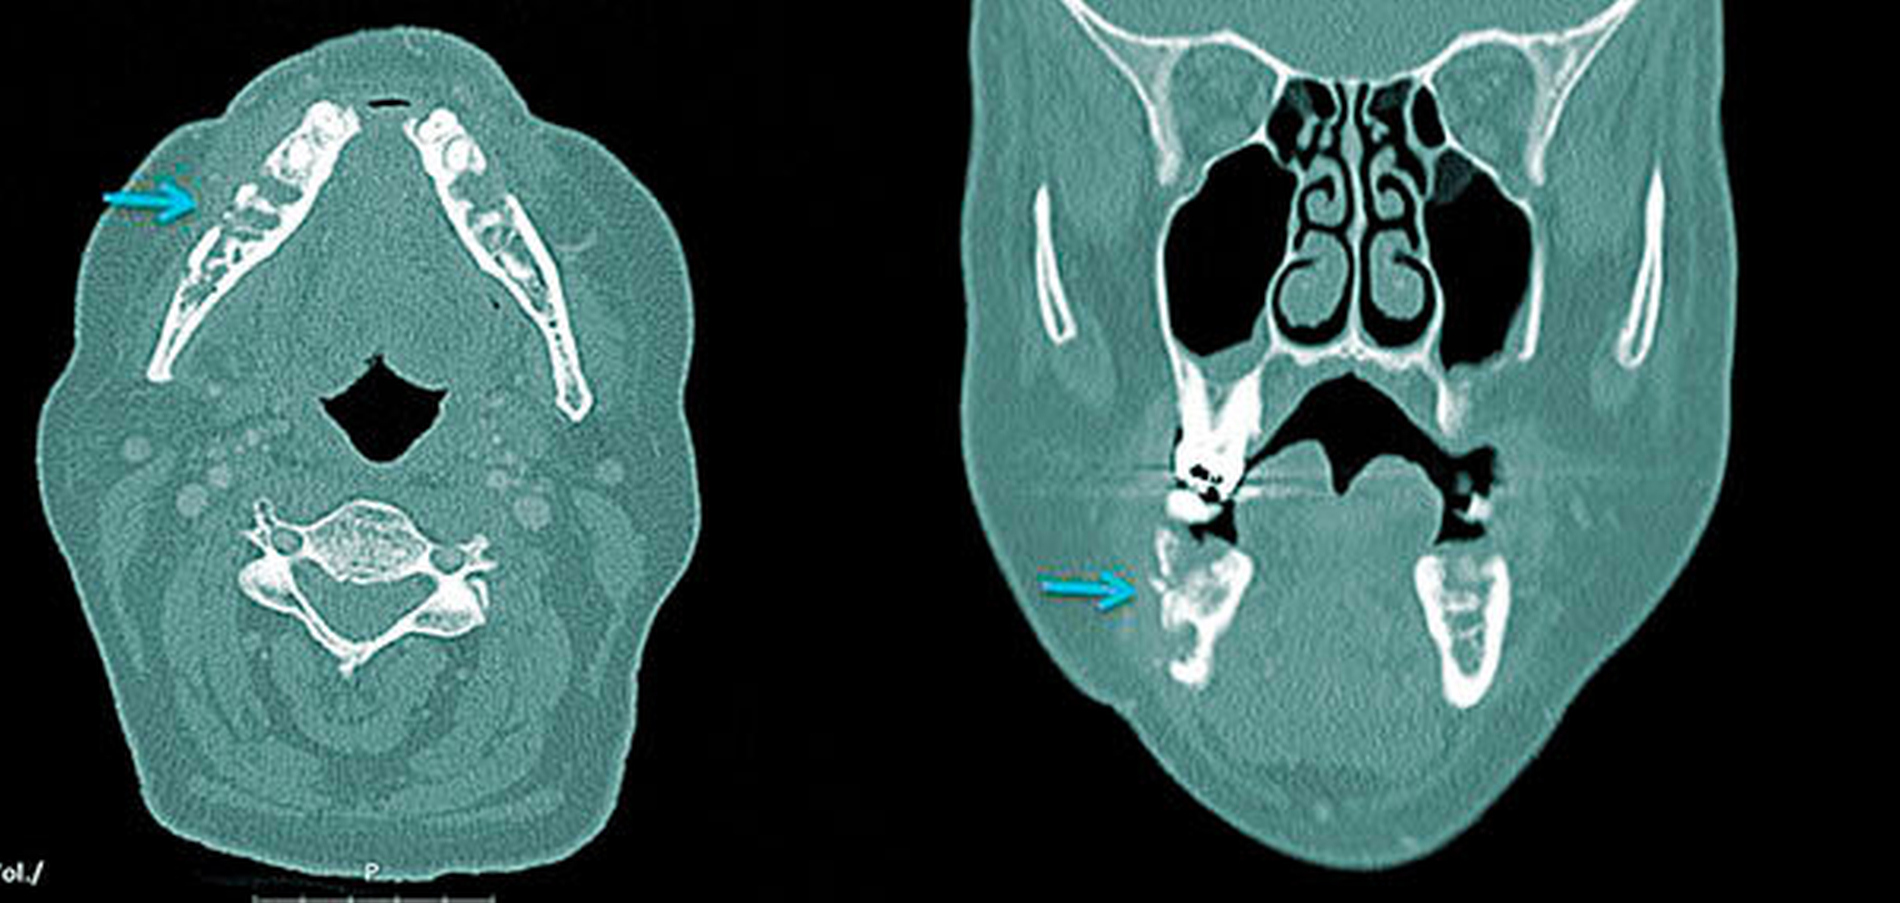

Entsprechend der Definition der IORN ist die Diagnosestellung an eine gezielte Anamnese und klinische Untersuchung von Mundhöhle und Perioralregion gebunden. Neben der Inspektion und Palpation umfasst diese auch die Vitalitätsprüfung benachbarter Zähne sowie eine Sensibilitätsprüfung. Der die IORN fachlich behandelnde Arzt beziehungsweise Zahnarzt legt Ausmaß und Umfang der Diagnostik (dreidimensionale Bildgebung) fest. Das Orthopantomogramm (OPTG) weist im Vergleich zu schichtbildgebenden Verfahren (Computertomografie, Magnetresonanztomografie) eine reduzierte Sensitivität auf [Store und Larheim, 1999]. Wichtigste Differenzialdiagnose der IORN ist ein malignes Geschehen (zum Beispiel Rezidiv, Metastase), weswegen eine histologische Sicherung erfolgen sollte [Marwan et al., 2014].

Bei klinischem Verdacht auf eine IORN soll eine histologische Sicherung zum Ausschluss eines malignen Geschehens erfolgen.